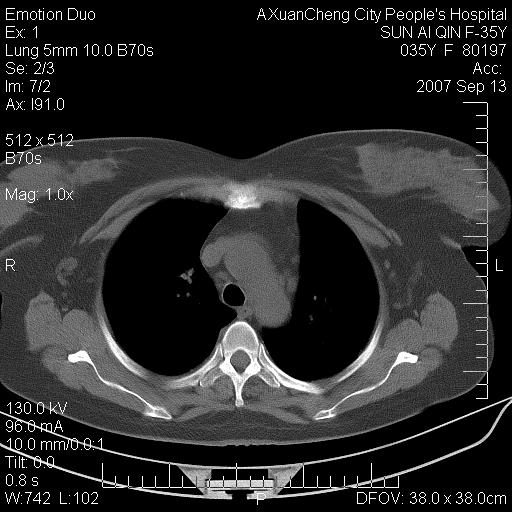

以下是引用天南地北在2007-9-13 13:43:00的发言:[br]考虑双肺、肺门侵润

以下是引用ydx_74在2007-9-13 15:42:00的发言:[br]仅看片,考虑右上肺癌并双肺转移,结合病史,考虑肺门、肺内淋巴侵润

以下是引用同在2007-9-13 15:08:00的发言:[br]支持肺门及双肺侵润.